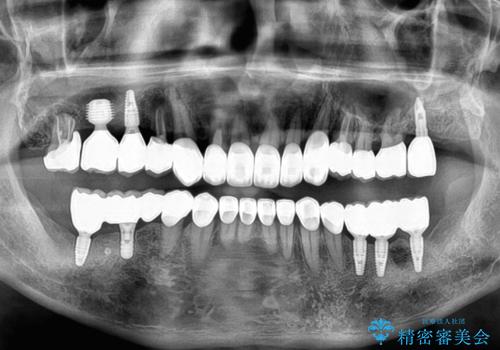

欠損部はインプラントによる補綴治療を行うこととし、臼歯部が安定した後に、上下前歯部をオールセラミッククラウンにて補綴治療を行うこととしました。

上顎前歯に歯周ポケットの深い部分がありましたが、インプラントの仮歯で奥歯がしっかりと噛めるようになると、1年程度で深い歯周ポケットは解消されました。

前歯部の審美面も大幅に改善され、大変満足していただけました。